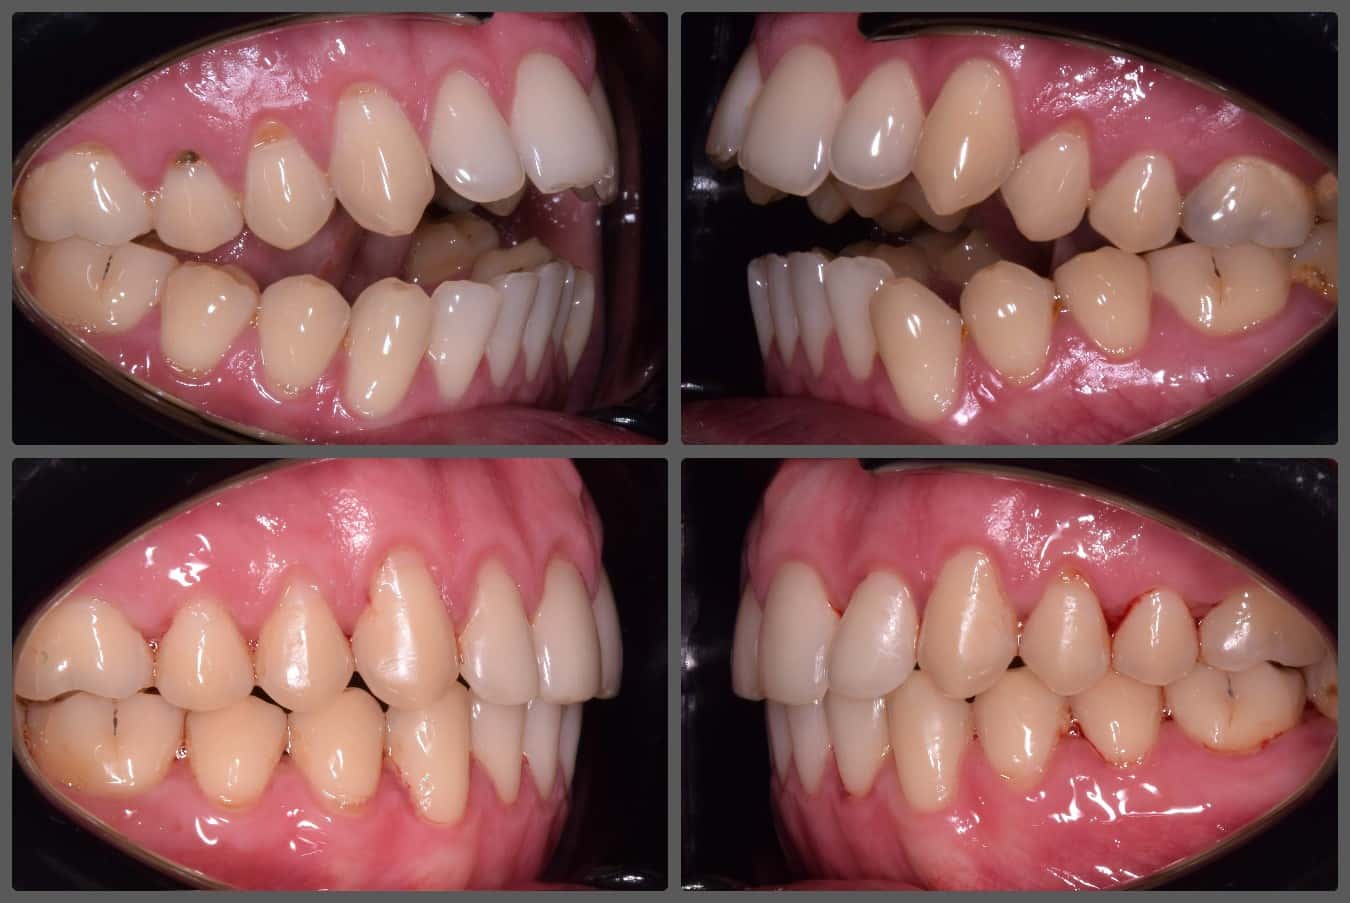

Bálint a 90 fokban elfordult jobb felső kismetszője miatt keresett meg engem. A vizsgálatokat követően kiderült, hogy a probléma ennél jóval komplexebb: súlyos keresztharapást, súlyos mélyharapást és felső rágósík billenést diagnosztizáltam nála. Alsó-felső H4 önligírozó fogszabályozó készülék, intermaxilláris gumihúzás és elülső harapásemelők segítségével korrigáltuk az eltéréseket. A bal oldali rágósík billenést fogszabályzási miniimplantátum alkalmazásával oldottuk meg. A bal felső-elülső fogakat felfelé mozgattuk, a miniimplantátumhoz húzva. Bálint esete igen komplex volt, ám kiváló együttműködésének köszönhetően 26 hónap alatt végeztünk a kezelésével (beleértve a 2-3 hónapos COVID-19 miatti leállást is). Az eredmény úgy gondolom magáért beszél!